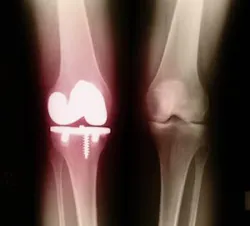

Glucosamine and chondroitin are somewhat helpful to treat pain and the loss of function associated with osteoarthritis in joints. Glucosamine usually is derived from the shells of shellfish. Chondroitin comes from cartilage, usually from shark and cow cartilage. Combined, they have been shown to rebuild human cartilage around joints, although the FDA has not allowed such a health claim. Some studies show chondroitin offers about an 8-10-percent joint mobility improvement, although it works slowly (three months or more).